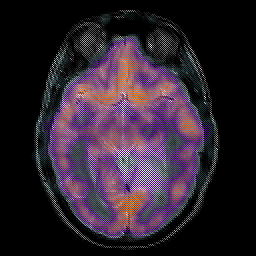

Glioma overlay -- Slice #12

[Home][Help][Clinical] Slice 12